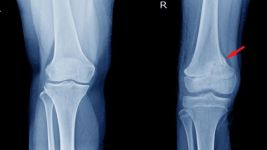

Funkcija i značaj čašice (patela) u ljudskom telu

Šta je patela?

Fraktura patele je ozbiljna povreda kolena koja zahteva odgovarajuće lečenje, konzervativno ili hirurško, kako bi se obnovila funkcija. Pravovremena...

Simptomi, dijagnostika i lečenje Bekerove ciste

Šta je Bekerova cista?

Bekerova cista, otok ispunjen tečnošću na zadnjem delu kolena, često nastaje zbog otoka sinovijalne tečnosti. Dijagnoza uključuje klinički...